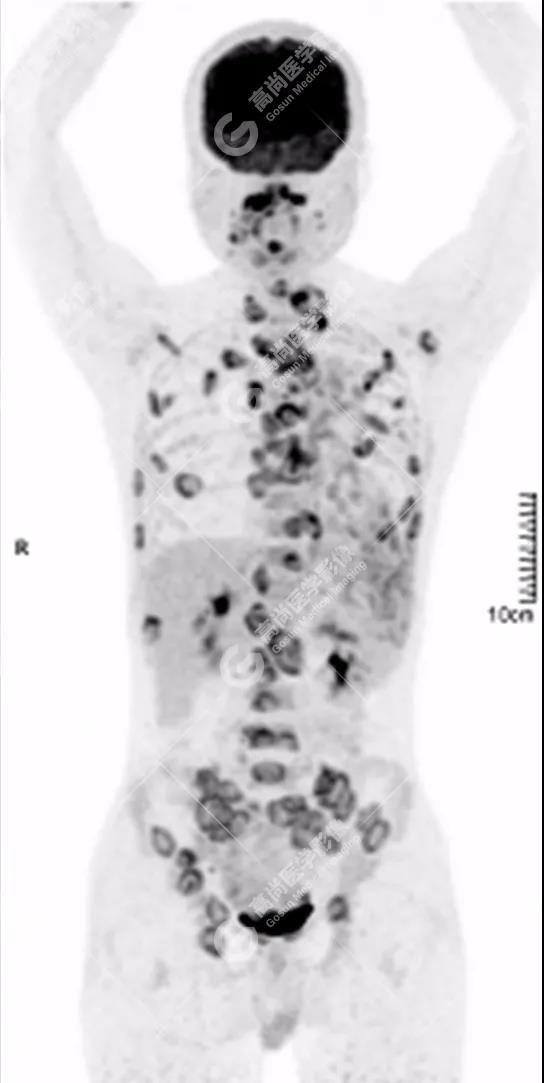

PET/CT全身圖

脊柱多發(fā)椎體及附件骨質破壞,代謝不均性增高

全身多處骨質破壞,代謝不均性增高

全身多發(fā)高代謝腫大淋巴結,中央代謝缺損

雙肺、左側胸膜多發(fā)結節(jié)影,全身多處骨質破壞,全身多發(fā)淋巴結腫大,代謝攝取不均勻性增高。